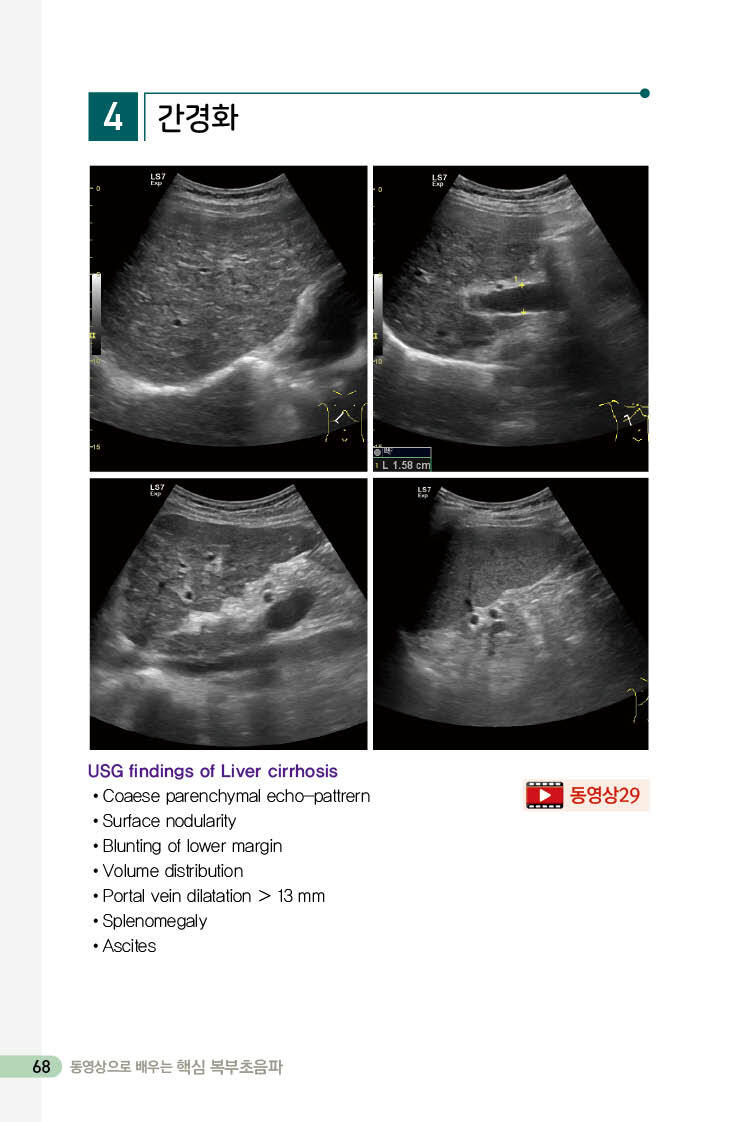

간경화 68

1. 간 실질의 에코 142

2. 간 표면의 요철 143

3. 간의 밝기 144

4. 간의 크기 145